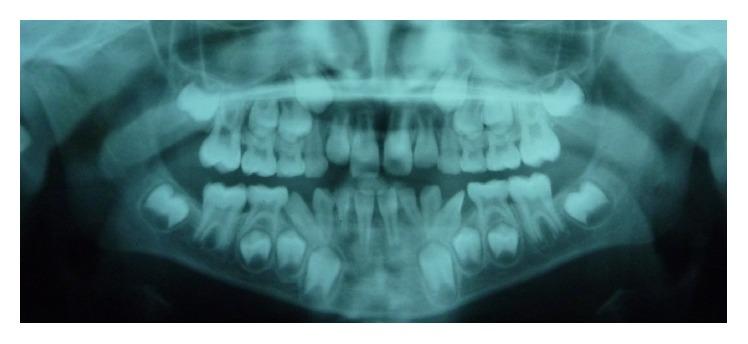

Bilateral mandibular tooth transposition is a relatively rare dental anomaly caused by distal migration of the mandibular lateral incisors and can be detected in the early mixed dentition by radiographic examination. Early diagnosis and interceptive intervention may reduce the risk of possible transposition between the mandibular canine and lateral incisor. This report illustrates the orthodontic management of bilateral mandibular canine-lateral incisor transposition. Correct positioning of the affected teeth was achieved on the left side while teeth on the right side were aligned in their transposed position. It demonstrates the outcome of good alignment of the teeth in the dental arch.

双侧下颌牙齿易位是一种相对罕见的牙齿异常,由下颌侧切牙向远中移位引起,可通过影像学检查在混合牙列早期发现。早期诊断和阻断性干预可能会降低下颌尖牙和侧切牙之间可能发生易位的风险。本报告阐述了双侧下颌尖牙-侧切牙易位的正畸治疗。左侧患牙实现了正确定位,而右侧牙齿则在其易位位置排齐。它展示了牙弓中牙齿良好排齐的效果。